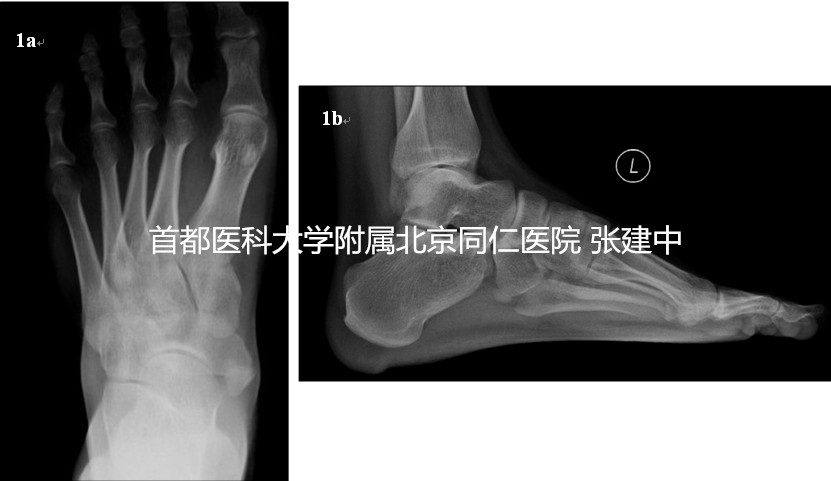

图1. 1a. 患足负重正位X线,示II型副舟骨存在;1b. 患足负重侧位X线,示副舟骨存在及足弓情况

患者,女,43岁,因“左足内侧疼痛7年”来诊。患者7年前不明原因出现左足内侧疼痛,行走及劳累后加重。查体:患足平足,足弓塌陷。足内侧舟骨结节处稍膨隆,为骨性突起,压痛位于舟骨结节膨隆处而非胫后肌腱走行区及止点。余无异常表现(图1)。负重位X线示左足存在副舟骨,为II型;为进一步明确副舟骨疼痛原因为腱性还是骨性,行SPECT-CT检查,结果回示副舟骨与舟骨关节部位核素浓聚,代谢增高(图2),提示关节局部存在炎性变。诊断为II型副舟骨,且判断其症状来源位于舟骨与副舟骨之间关节处。